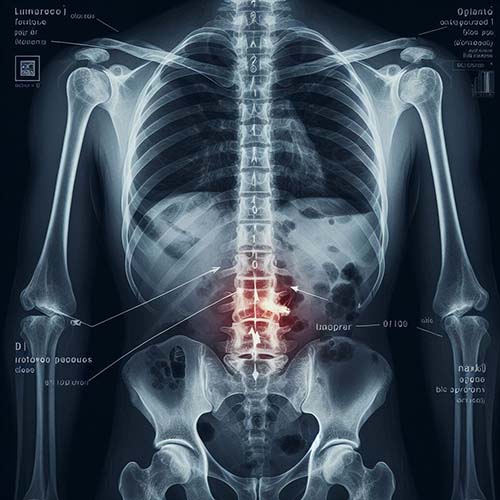

척추 압박 골절이란 무엇인가요?

척추 압박 골절은 척추의 척추뼈가 압박력으로 인해 주저앉거나 골절될 때 발생하며, 주로 골다공증과 관련이 깊습니다. 이 질환은 뼈가 약해지는 골다공증과 관련이 있는 경우가 많은데요, 골다공증은 뼈가 약해지는 것을 특징으로 하는 현상입니다. 그러나 외상, 종양 또는 기타 근본적인 의학적 문제로 인해 발생할 수도 있지만, 그 외 다른 원인으로 인해 발생할 수도 있습니다.